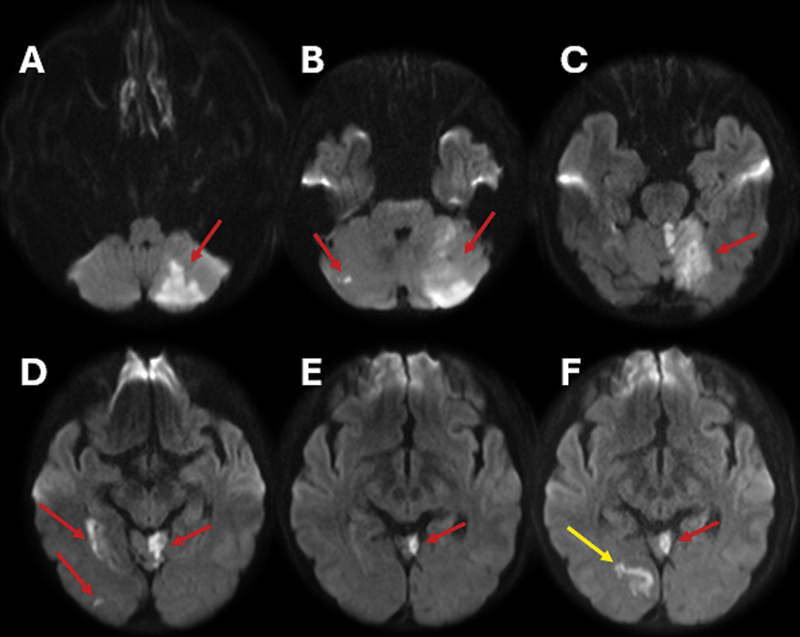

Unmasking vertebral artery stump syndrome in recurrent posterior strokes treated with endovascular therapy.